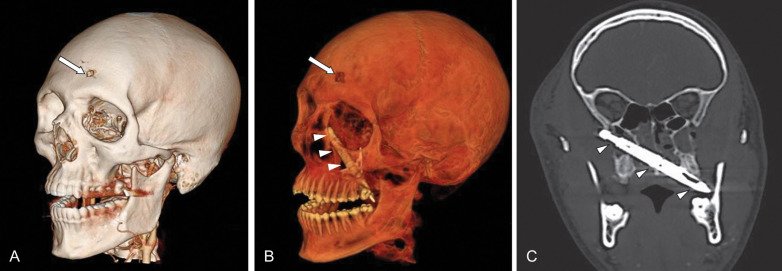

In comparison to plain radiographs of the face, CT eliminates the superimposition of structures and provides high-resolution contrast of the osseous structures and soft tissues that can be viewed simultaneously in three orthogonal planes as well as 3D ( Figs. 1.2.3–1.2.7 ). This allows for complete evaluation of the face, skull base, cranium, and brain. In a large study, it was reported that the most common fractures were to the midface (71.5%) with supraorbital and frontobasal skull fractures present in 4.2% of the cases. CT is superior to plain radiographs when assessing the mandible, especially nondisplaced symphyseal fractures, given the overlapping spine on the AP Towne’s view. CT has a higher accuracy, sensitivity, and specificity (90%, 90%, 87%, respectively) for condylar fractures when compared to panoramic radiographs (73%, 70%, 77%, respectively). CT has also been shown to detect additional fractures not seen on plain or panoramic radiographs, often leading to a change in operative management. In the setting of penetrating trauma, multidetector CT is the best imaging modality to assess the trajectory of the missile and injury to the adjacent soft tissues and vascular structures ( Fig. 1.2.8 ).